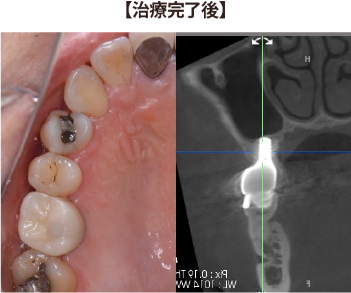

①右上6番が無く、骨の高さが少ない症例

骨の高さが少し足りず、このままではインプラントが骨からはみ出てしまう。

インプラント埋入と同時に骨の高さを増やす手術(上顎洞底挙上術)を併用し、

1回の手術でインプラントを埋入できました。

数か月ほど骨との結合を待った後に、かぶせ物を製作しています。

数年経過しても、全く違和感なく食事を楽しめています。

| 治療期間 : | 3ヶ月 |

| メリット : | ブリッジや入れ歯に比べて、両隣の歯を削ること無く、強い歯を再建することができる。 入れ歯やブリッジに比べて自然なかみ合わせを得られる。 概して入れ歯やブリッジより長持ちし、他の残存歯における負担も減らすことで、残存歯本来の寿命を全うできることが多い。 虫歯にならない。 |

| リスク・副作用 : | 手術が必要であり、感染のリスクを伴う。 術後に一時的に腫れたり痛みが出ることがある。 治療完了までに数か月の期間を要する。 自費治療であり、保険治療より高額である。 インプラントも歯周病になることがある。 |

| 費用(自費治療分): | 合計金額 ¥473,000(税込) (ソケットリフト法併用、SLActive加算、ジルコニア冠の場合) |